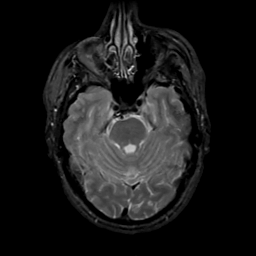

MR Study #4, March 3, 1991 -- Slice #15

[Home][Help][Clinical][Tour 1][Tour 2] Slice 15